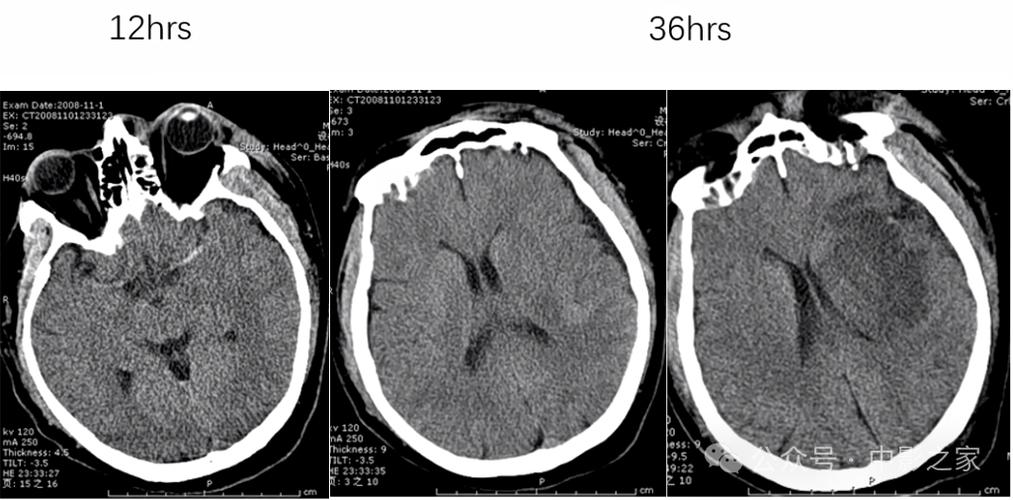

在脑梗发生的早期(通常在6小时内),普通的CT扫描很难直接显示出脑梗的病灶,因为在这个阶段,脑组织只是缺血,细胞水肿还非常轻微,密度变化不大,CT上可能完全正常,或者只有一些非常细微、难以察觉的征象。

如果发病时间超过6-24小时,随着脑细胞开始死亡、水肿加重,CT上就可能出现一些异常信号,医生可以据此判断脑梗的可能性,这些早期间接征象包括: